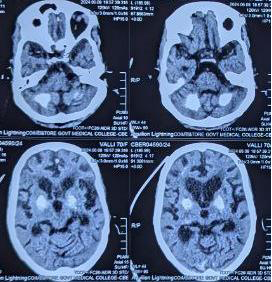

MRI brain was suggestive of coarse calcification in bilateral

basal ganglia, dentate nuclei and occipital gyri. She had low normal

serum calcium level. With elevated parathormone levels and vit-D3

Figure 1: CT- brain showing bilateral symmetric calcification of basal ganglia

and dentate nucleus of cerebellum

Imaging varies: While many cases report normal MRIs or nonspecific changes, some describe white matter changes or atrophy. Unusually, this case features coarse calcifications in basal ganglia, dentate nuclei, and occipital gyri, meeting radiological criteria for Fahr’s syndrome.[1,4]